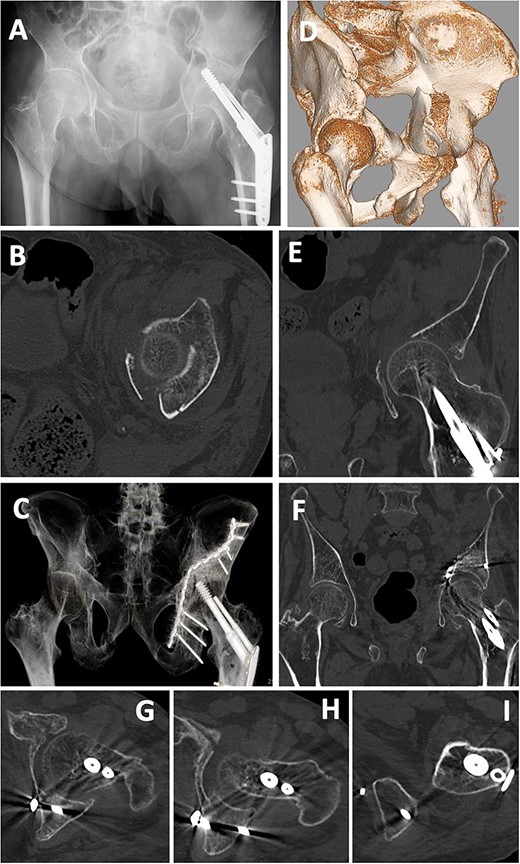

A 55-year-old man was involved in a motorcycle accident and taken to a nearby hospital. Diagnostic imaging showed a left acetabular fracture (Fig. 6A, C, D, F–J; both column fractures according to the AO classification). He was transferred to our hospital, and 12 days after the injury, open reduction and internal fixation were performed using a low-profile pelvic plate system (DePuySynthes Trauma, West Chester, PA, USA). The patient was placed in the supine position, and the classical ilioinguinal approach was used. The skin was cut from the pubic joint to the iliac crest, the abdominal muscles were released, and the retroperitoneal area and the fracture area were reached. Dislocation of the pelvic brim was reduced with a reduction clamp and fixed by a screw. After the internal obturator muscle was retracted, the quadrilateral fragment was reduced, a bent 12-hole, one-third plate was placed at the quadrilateral surface, and a screw was inserted from the posterior column to the ilium using the sleeve guide technique (Fig. 6K–O). In addition, two reconstruction plates were used for fixation from the anterior to the posterior ilium and from the pubis to the ilium (Fig. 6B, E). Six weeks after the operation, partial weight-bearing was started. After 3 months, the patient walked with a stick. After 1 year, he reported no hip or pelvic pain, and he walked without a gait abnormality.

Case 1 images: (A) pre-operative X-ray, (B) post-operative X-ray, (C) pre-operative 3D-CT (anterior), (D) pre-operative 3D-CT (posterior), (E) post-operative 3D-CT, (F–J) pre-operative axial CT images, (K–O) post-operative axial CT.

A 66-year-old man, who walked with a stick, was injured in a fall during a sudden convulsion. He could not move his left lower extremity due to pain and rested in his house. After 3 days, he developed a fever (>38°C) and was admitted to a nearby hospital. Diagnostic imaging showed a quadrilateral fracture (Fig. 7A, B, D, E). Twelve days after injury, open reduction and internal fixation for the acetabular fracture were performed using a low-profile pelvic plate system by the classical ilioinguinal approach, as in case 1. After a 13-hole reconstruction plate was bent and placed at the quadrilateral surface, screws were inserted to the posterior column and ischium using the sleeve guide technique (Fig. 7C, F–I). Six weeks after the operation, partial weight-bearing was started. After 3 months, he was able to walk with a rollator, and after 1 year, he walked with a stick.

Case 2 images: (A) pre-operative X-ray, (B) pre-operative axial CT image, (C) post-operative X-ray, (D) pre-operative 3D-CT, (E) pre-operative coronal CT image, (F) post-operative 3D-CT, (G–I) post-operative axial CT images. Screws are inserted into the posterior wall (G, H) and near the ischial tuberosity (I).